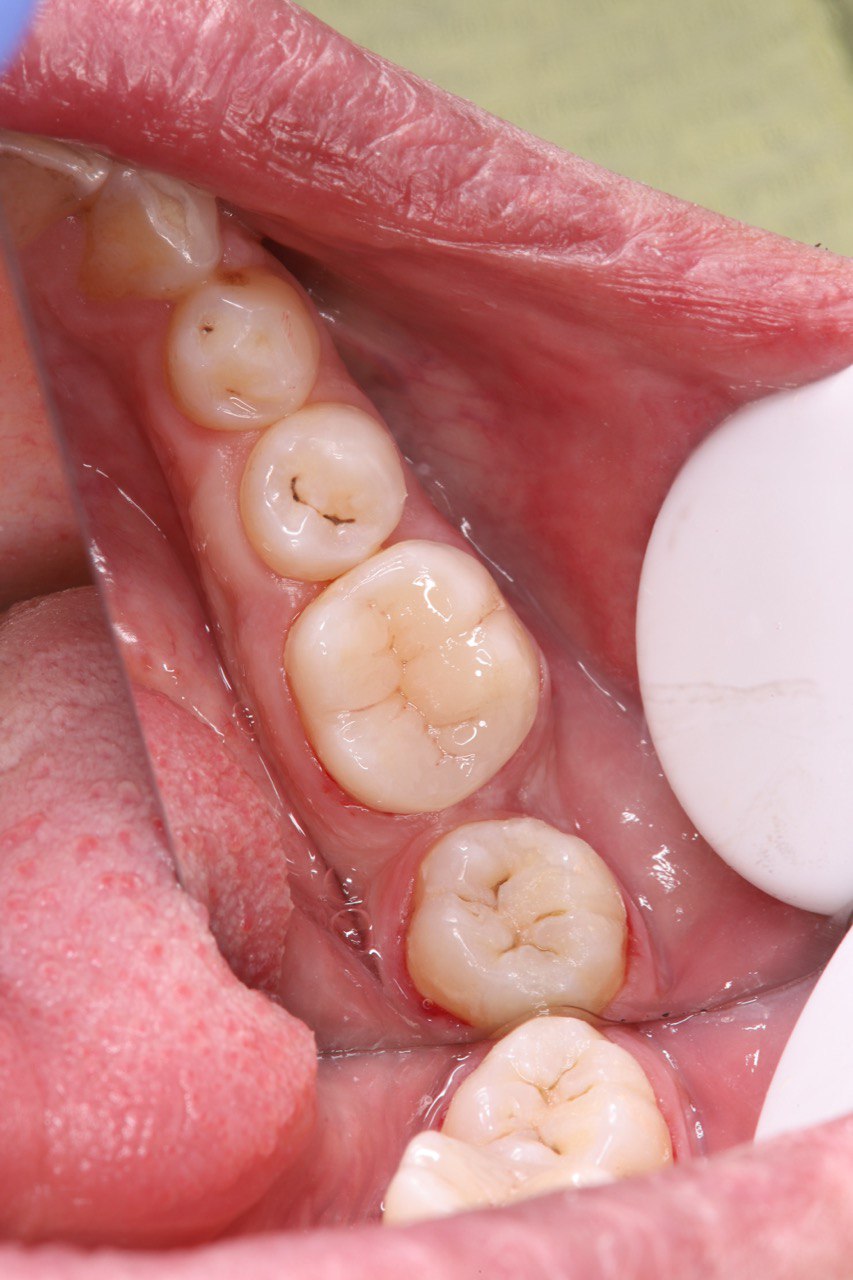

Пациент обратился с жалобами на разрушение пломбы на 6 зубе. Часть пломбировочного материала была сколота, оставшаяся часть утратила герметичность.

Проведённое лечение

Удалена старая пломба

Проведено полное удаление кариозных тканей

Зуб подготовлен к восстановлению

Выполнена реставрация фотополимерным материалом

Восстановлена анатомическая форма жевательной поверхности

Герметичность и функция зуба полностью восстановлены